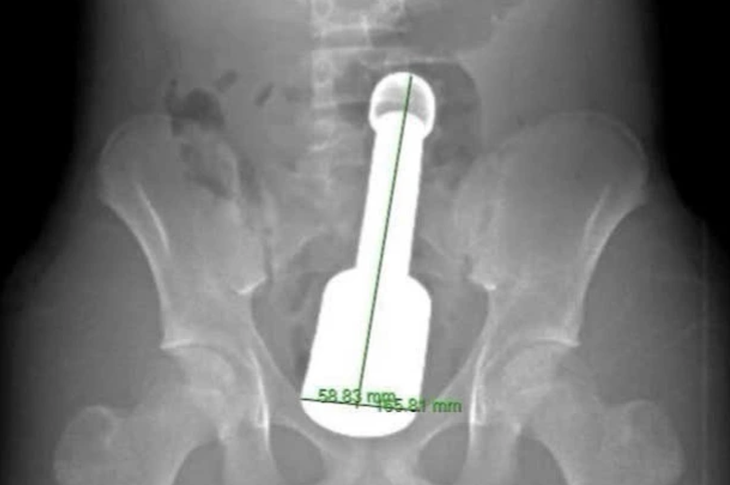

Hình ảnh chụp X-quang và dị vật được lấy ra khỏi hậu môn của bệnh nhân - Ảnh: BVCC

Dị vật là một chiếc chày dài 18cm, đường kính 6cm. Thử thách lớn nhất đối với kíp mổ là dị vật quá to so với cơ thắt hậu môn của thiếu niên, đồng thời tạo ra "hiệu ứng chân không" khiến nó bị hút chặt vào lòng ruột.

Sau 45 phút, dị vật đã được lấy ra an toàn. Vùng tổn thương chỉ bị trầy xước nhẹ, chức năng cơ thắt hậu môn được bảo tồn hoàn toàn.